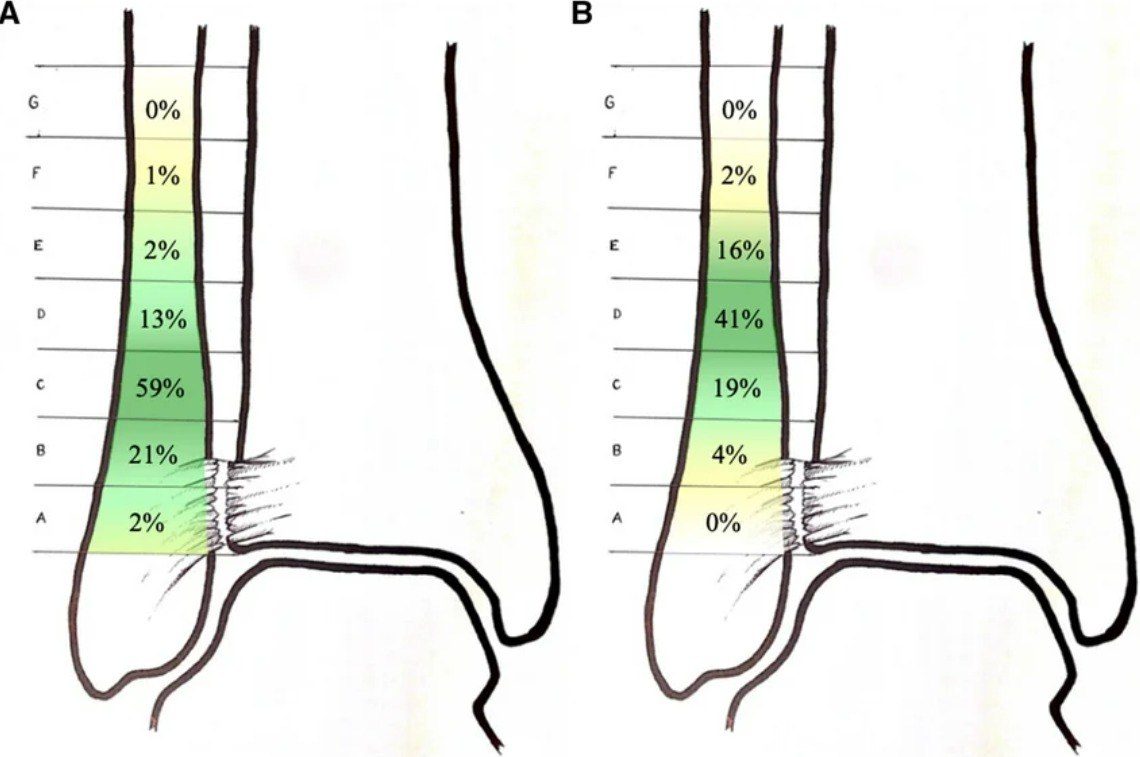

Рис. 21. Варианты фиксации межберцового синдесмоза

Рис. 22. Зона установки позиционных винтов по результатам опроса хирургов. А — установка первого винта, В — установка второго винта

Количество кортикалей при винтовой фиксации. Вопрос о том, сколько кортикалей должен захватывать позиционный винт, также остаётся дискуссионным. Биомеханические исследования и клинические данные не выявили значимых различий между трикортикальной и квадрикортикальной фиксацией ни по механической прочности, ни по функциональным результатам, ни по рентгенологическим параметрам. Трикортикальная фиксация рассматривается как адекватная альтернатива с сопоставимыми результатами.

Интраоперационный контроль репозиции. Проспективное исследование с использованием интраоперационной 3D-визуализации (O-arm или моторизованная 3D С-дуга) показало, что при удовлетворительной флюороскопической картине 3D-контроль выявлял подвывих, требующий ревизии, в 41% случаев. Это подчёркивает недостаточность стандартной флюороскопии и необходимость расширенного контроля репозиции.